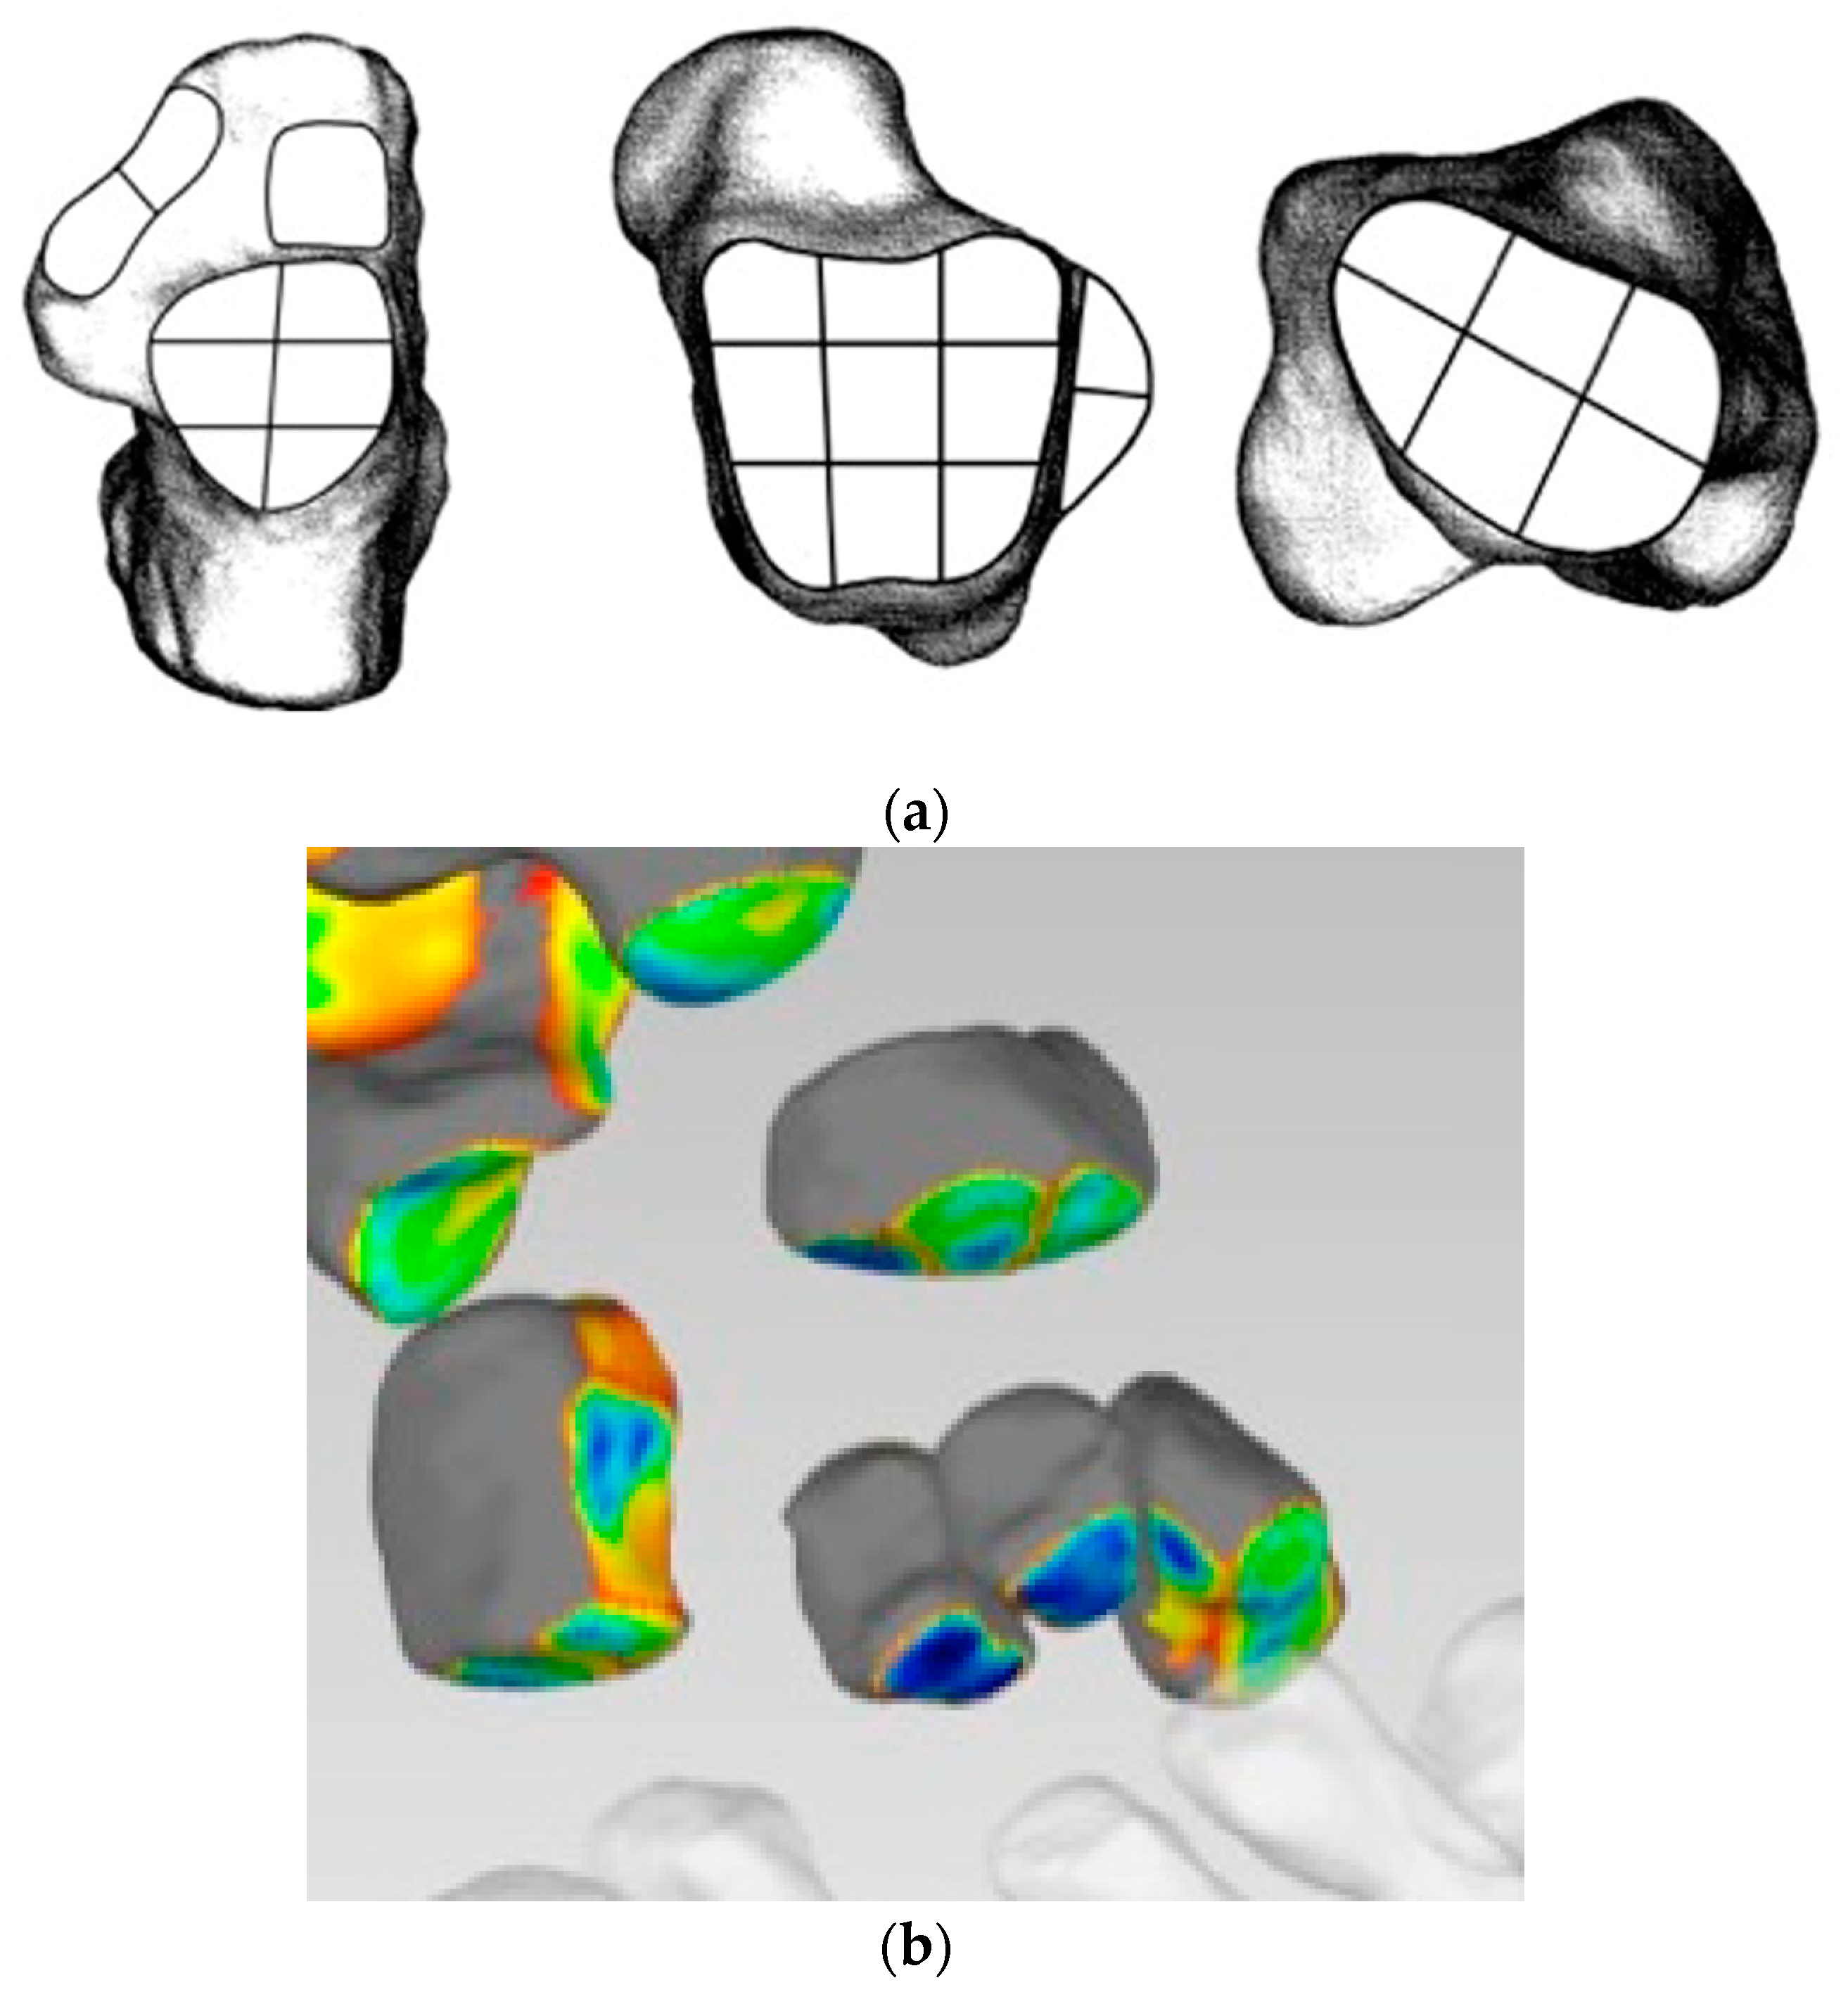

- Distance Mapping or 3D-JSW, surface and volume measurements

- Coverage Mapping

- Bernasconi, A.; De Cesar Netto, C.; Siegler, S.; Jepsen, M.; Lintz, F.; International Weight-Bearing CT Society. Weightbearing CT assessment of foot and ankle joints in Pes Planovalgus using distance mapping. Foot Ankle Surg. 2022, 28, 775–784. [Google Scholar] [CrossRef]

- Lintz, F.; Jepsen, M.; De Cesar Netto, C.; Bernasconi, A.; Ruiz, M.; Siegler, S.; International Weight-Bearing CT Society. Distance mapping of the foot and ankle joints using weightbearing CT: The cavovarus configuration. Foot Ankle Surg. 2021, 27, 412–420. [Google Scholar] [CrossRef]

- Dibbern, K.N.; Li, S.; Vivtcharenko, V.; Auch, E.; Lintz, F.; Ellis, S.J.; Femino, J.E.; de Cesar Netto, C. Three-Dimensional Distance and Coverage Maps in the Assessment of Peritalar Subluxation in Progressive Collapsing Foot Deformity. Foot Ankle Int. 2021, 42, 757–767. [Google Scholar] [CrossRef]